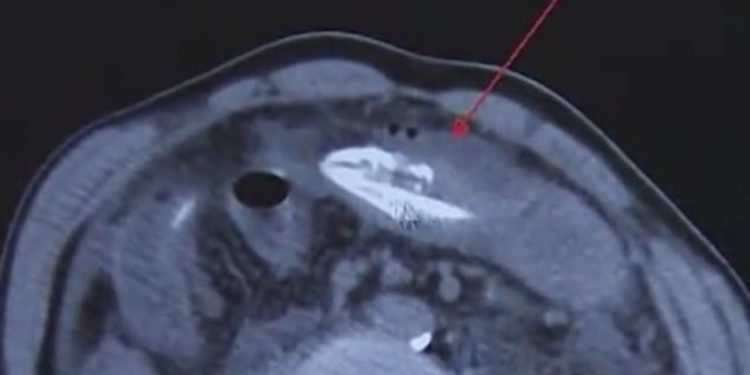

Τουλάχιστον… αυτό είπε στους γιατρούς, οι οποίοι έμειναν με το στόμα ανοικτό αντικρίζοντας τις πρωτοφανείς εικόνες από την ακτινογραφία.

Σύμφωνα με την dailymail.co.uk πρόκειται για χέλι, μήκους σχεδόν 20 εκατοστών, το οποίο όχι μόνο ήταν ακόμα ακόμα ζωντανό, αλλά κατάφερε να φτάσει μέχρι την κοιλιά του άτυχου άνδρα, ο οποίος λίγο έλειψε να βρει τραγικό θάνατο, αναζητώντας εναλλακτικές ιατρικές θεραπείες.

Σύμφωνα επίσης με τους γιατρούς, το χέλι, το οποίο εξερεύνησε το πιο παράξενο και αφιλόξενο μέρος που έχει βρεθεί ποτέ, δάγκωσε το έντερο του Κινέζου, ο οποίος ισχυρίζεται ότι η θεραπεία που επέλεξε βασίζεται σε ένα παλιό παραδοσιακό γιατροσόφι για την καταπολέμηση των προβλημάτων του παχέος εντέρου.